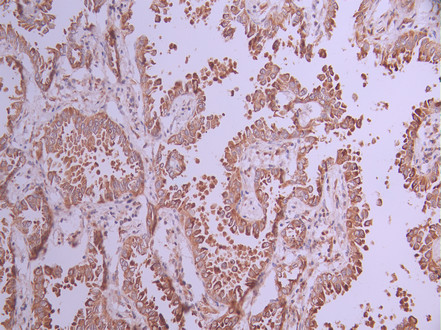

IHC image of CSB-RA976601A0HU diluted at 1:100 and staining in paraffin-embedded human lung cancer performed on a Leica BondTM system. After dewaxing and hydration, antigen retrieval was mediated by high pressure in a citrate buffer (pH 6.0). Section was blocked with 10% normal goat serum 30min at RT. Then primary antibody (1% BSA) was incubated at 4°C overnight. The primary is detected by a Goat anti-rabbit polymer IgG labeled by HRP and visualized using 0.05% DAB.

IHC image of CSB-RA976601A0HU diluted at 1:100 and staining in paraffin-embedded human liver tissue performed on a Leica BondTM system. After dewaxing and hydration, antigen retrieval was mediated by high pressure in a citrate buffer (pH 6.0). Section was blocked with 10% normal goat serum 30min at RT. Then primary antibody (1% BSA) was incubated at 4°C overnight. The primary is detected by a Goat anti-rabbit polymer IgG labeled by HRP and visualized using 0.05% DAB.